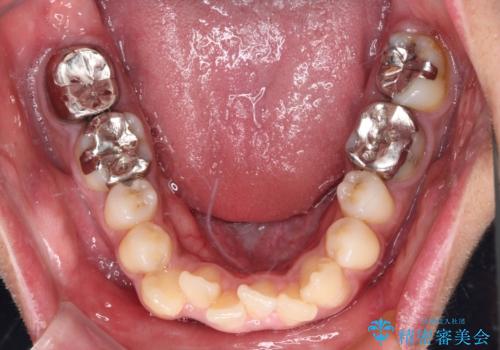

- 前歯のデコボコと八重歯、開咬を気にして来院された患者様です。

骨格的に下顎骨が上顎骨に対して後退位であったため、上顎の左右第一小臼歯を抜歯し、デコボコを改善するとともに開咬を改善していくこととしました。

舌の突出癖により開咬となっていたため、突出癖改善のためのトレーニングをしっかりと行っていただき、予定の期間で無事に治療を終えることができました。